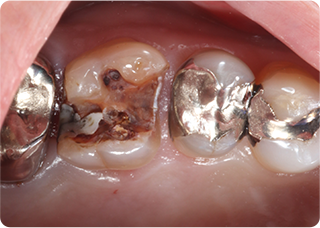

セラミックオーバーレイ症例①

術前

術中

術後

| 主訴 | むし歯の歯を治療をしたい |

|---|---|

| 治療期間/回数 | 3週間、3回 |

| 価格(税込) | 77,000円(税込) |

| リスク・副作用 | セラミックの破損、一時的な知覚過敏が生じる場合がある |

| ポイント | ラバーダム防湿下で接着することにより、歯とセラミックが一体化することを狙った。オーバーレイにすることで、歯ぐきに近い健康な歯質を削らずに治療することができる。 |